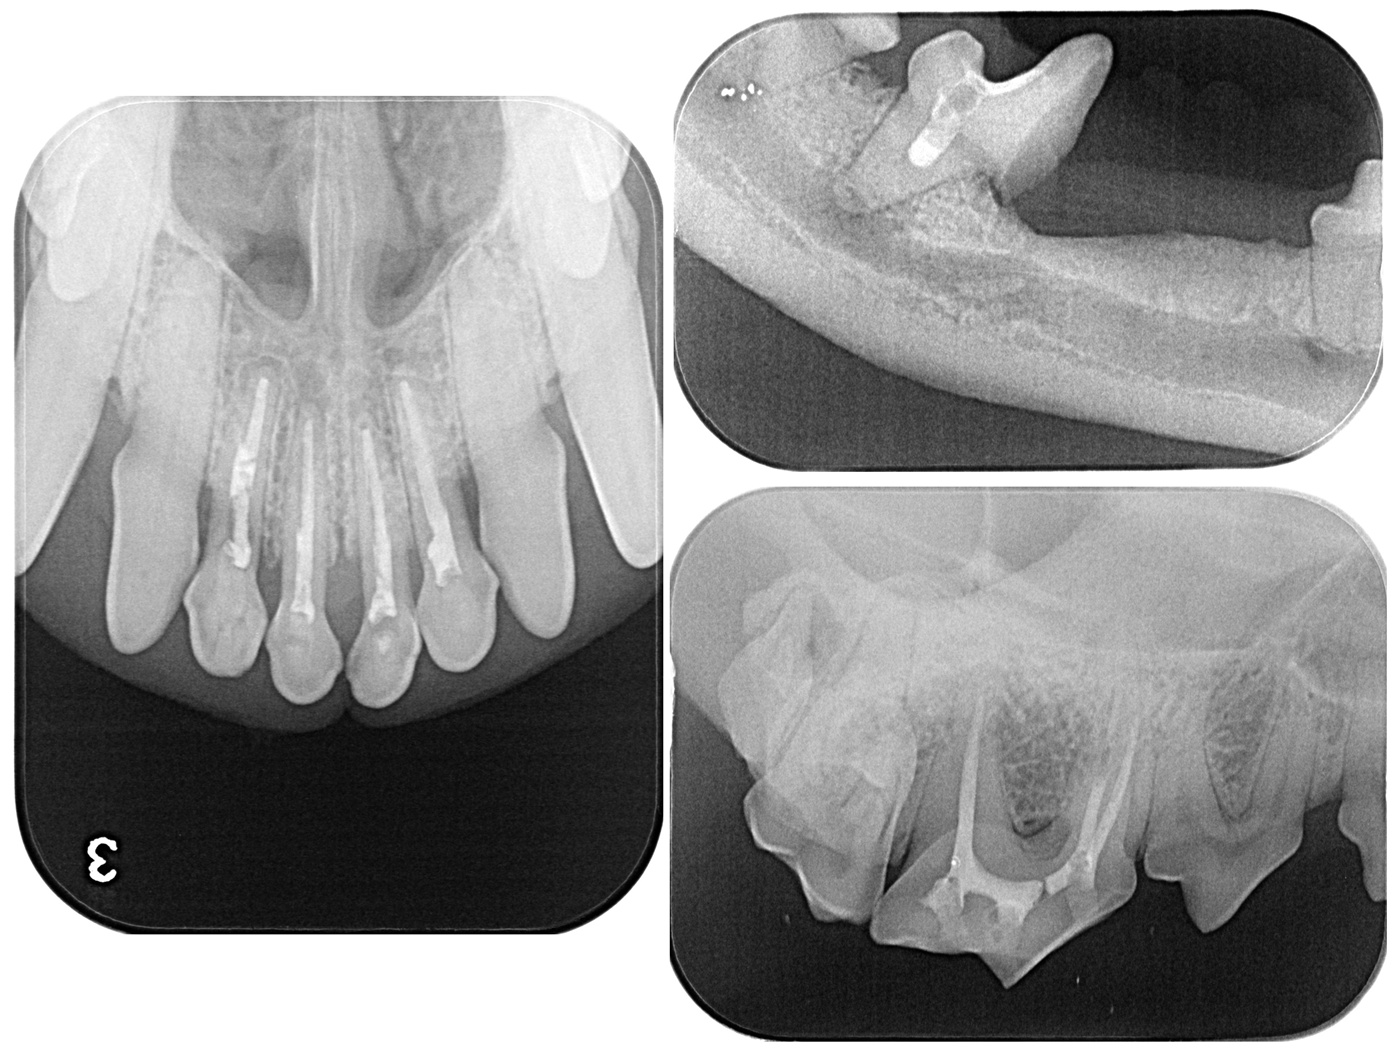

근관치료는 눈에 보이지 않는 복잡한 구조를 가진 치아 내부에서 치수 조직과 감염원을 제어하는 과정이다. 물리적으로 근관을 성형하여 감염된 치수 조직과 감염원을 제거하고, 강력한 소독약을 이용해 화학적으로 이를 제어한 뒤, 깨끗해진 근관을 빈틈없이 충전함으로써 더 이상 감염원이 유입되거나 치근단을 통해 교통되지 않도록 만드는 것이 이상적인 목표이다.

현재 수의치과학에서의 근관치료는 사람의 근관치료를 위해 개발되고 발전해 온 기구와 재료를 사용할 수밖에 없는 현실에 놓여 있다. 그러나 사람과 개, 고양이의 근관 해부학적 특성은 분명히 다르다. 따라서 이러한 기구와 재료를 개와 고양이의 근관 해부학에 맞게 적절히 변형(modification)하여 적용하는 것이 중요하다. 특히 사람에 비해 훨씬 복잡한 apical delta가 발달한 개와 고양이에서는 근단 1/3 부위를 얼마나 효과적으로 성형·세정·충전하는지가 높은 성공률을 좌우한다는 점이 최근 발표된 여러 문헌을 통해 확인되고 있다.